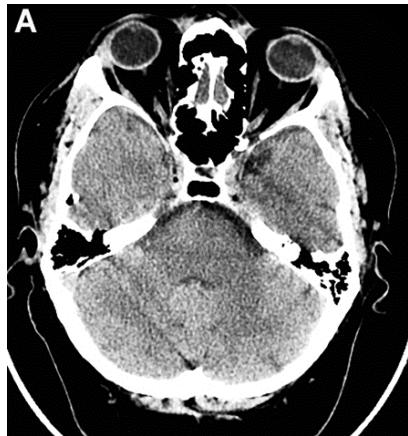

Figure 3: Same patient S., 42 years old, male.

A. Cerebral CT before transcatheter intracerebral laser PBMT: Total atrophy of the temporal lobes is $18\%$ of the total tissue volume (TDR-1). B. Cerebral CT in 12 months after transcatheter intracerebral laser PBMT: total atrophy of the temporal lobes decreased to $9\%$ of the total tissue volume (TDR-1). C. Cerebral CT in 4 years after transcatheter intracerebral laser PBMT: total atrophy of the temporal lobes decreased to $5.5\%$ of the total tissue volume.

The patient is transferred to AD group in TDR-0 stage.

According to the results of digital processing of CT and MRI images one year after the treatment, all 16 (100%) patients had an 8-10% decrease in the temporal lobes atrophy (Figures 3A, 3B). After 2-4 years, 13 (81.25%) patients showed a further 4-5.5% decrease in the temporal lobes atrophy leading to an almost complete restoration of the temporal lobe volume to the age norm (Figure 3B, 3C). Narrowing of the Sylvian fissures and restoration of the subarachnoid space accompanied the process. In accordance with the abovementioned criteria, all 16 (100%) patients were transferred to Group TDR-0.